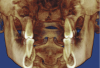

Figure 4A  Coronal section of 3D tomograph revealing axial alignment of posterior teeth. A) Dental alignment does not allow occlusal forces to be directed down long axis of teeth. Maxillary teeth had been tipped to the buccal to compensate for the transverse discrepancy. B) Teeth are positioned to allow occlusal forces to be directed down long axis of teeth.

Figure 4A

Figure 4B  Coronal section of 3D tomograph revealing axial alignment of posterior teeth. A) Dental alignment does not allow occlusal forces to be directed down long axis of teeth. Maxillary teeth had been tipped to the buccal to compensate for the transverse discrepancy. B) Teeth are positioned to allow occlusal forces to be directed down long axis of teeth.

Figure 4B